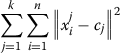

D. Classification

In this section, we examine fuzzy and non-fuzzy clustering algorithms and compare them with respect to their discrimination of overlapped nuclei. We use the k-means technique for the non-fuzzy approach, which was first introduced by McQueen [14]. The goal of this approach is to partition n-numbered observations into k sets. Since this method is non fuzzy, each of the pattern clusters have one center at any given time. This algorithm updates the centroids with each iteration to minimize the within-cluster sum of the squares, which is defined as

The fuzzy c-means (FCM) clustering method, was first introduced by Dunn in 1973 and then improved by Bezdek et al. in 1981. FCM is simply the optimization of the basic c-means objective function using a fuzzy approach. In contrast to k-means clustering, every observation has a degree of association with all sets, according to their distances apart, and observations do not belong to just one cluster. Every point has a set of coefficients [15], each of these coefficients represents a degree of association with one of the clusters, and the centroids of the clusters are the weighted means of the sets.

A point’s degree of belonging to a cluster is inversely proportional to the distance between a cluster centroid and the point. Accordingly, a greater distance means a lower degree of belonging to a set, calculated by:

![]() |

2 |

Where, uij is the degree of belonging of xi in the cluster j. Also, cj represents the center of each cluster which is determined by:

3 |

Clustering is determined by an iterative algorithm. Centers of the clusters and coefficients are updated upon each iteration until the change in coefficients is less than a given threshold. A block diagram of the algorithm we used is shown in Figure 6b. Ultimately, all observations are divided into two main clusters at the end of the iteration process.